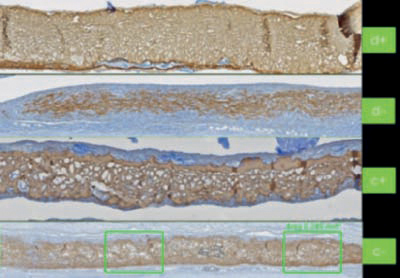

El proceso de limpieza patentado con dióxido de carbono supercrítico (scCO2) elimina suavemente los componentes no deseados (por ejemplo, células, lípidos) mientras que la matriz de colágeno natural y el entrelazado natural de las fibras de colágeno son preservados.

Una semana después de la implantación subcutánea en un músculo de rata: Smartbrane (M) ya está conectado al Tejido muscular (MT), sin signos de reacciones inflamatorias.

Dos semanas después de la implantación: los primeros vasos sanguíneos (BV) crecen hasta penetrar en Smartbrane (M), sin signos de reacciones inflamatorias.

Las fibras de colágeno (marrones) a los 14 días de implantación en normoglucemia (C-/C1) o grupos de diabéticos (d-/d+) cuando se usa con Hyadent BG (d+/c+) menor reabsorción de colágeno.